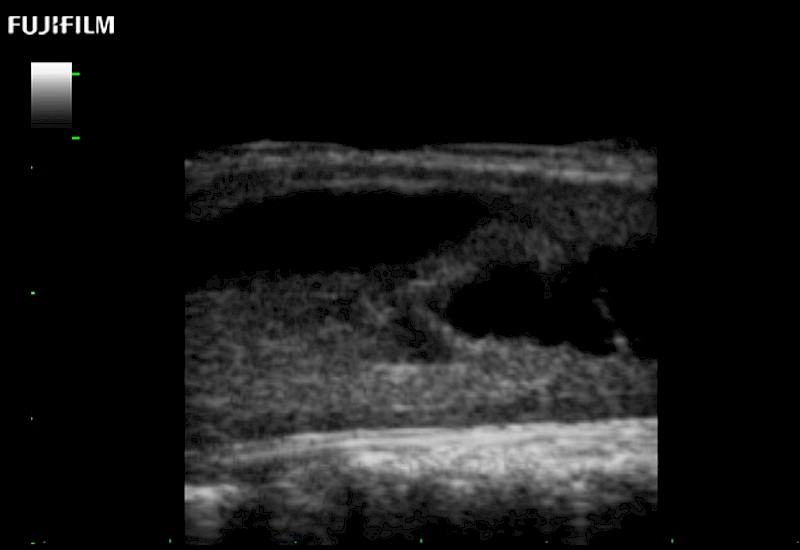

Hockey-stick linear array transducer is the transducer of choice for cervical spine scanning.

Main Specifications: